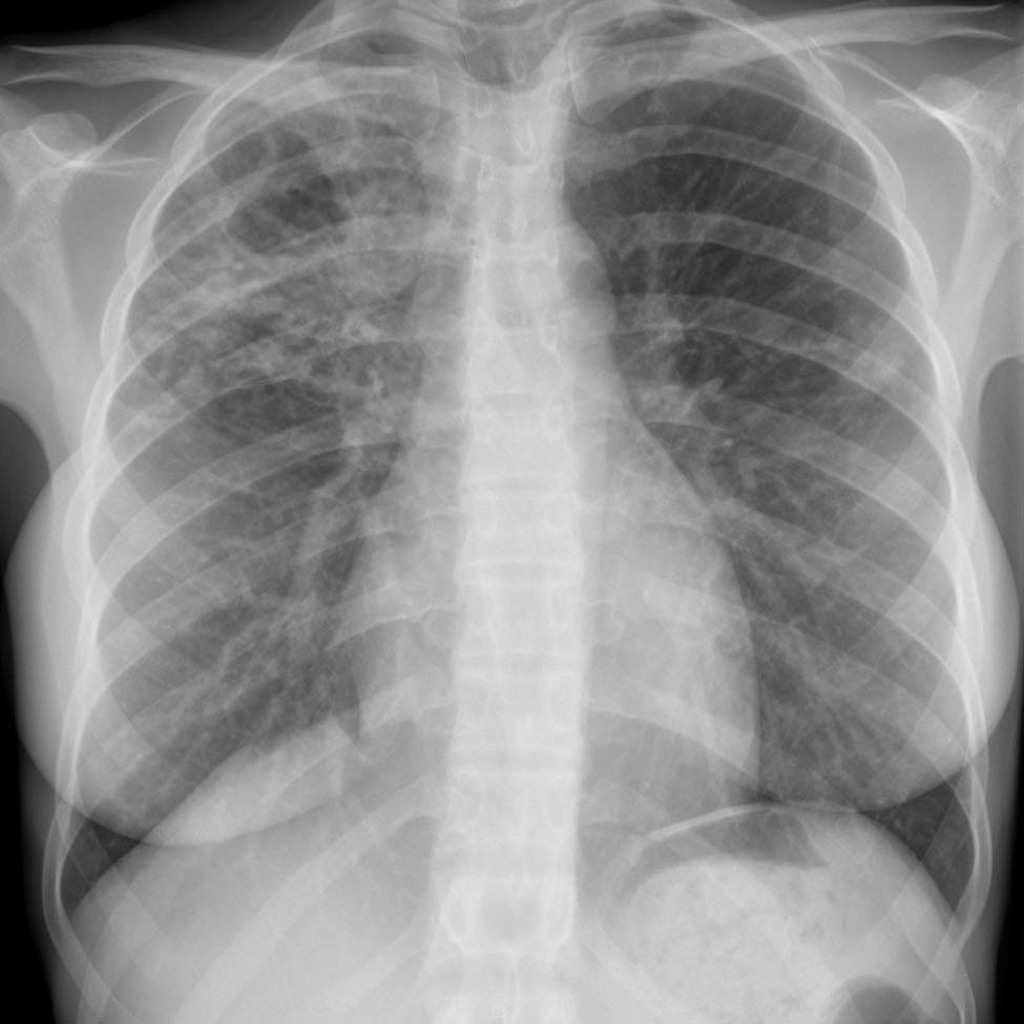

HOMEM, 50 ANOS, INTERNADO POR DISPNEIA + HEMOPTISE DE INÍCIO SÚBITO

áreas de opacidade em vidro fosco associadas a espessamento de septos interlobulares e intralobulares

HEMORRAGIA PULMONAR